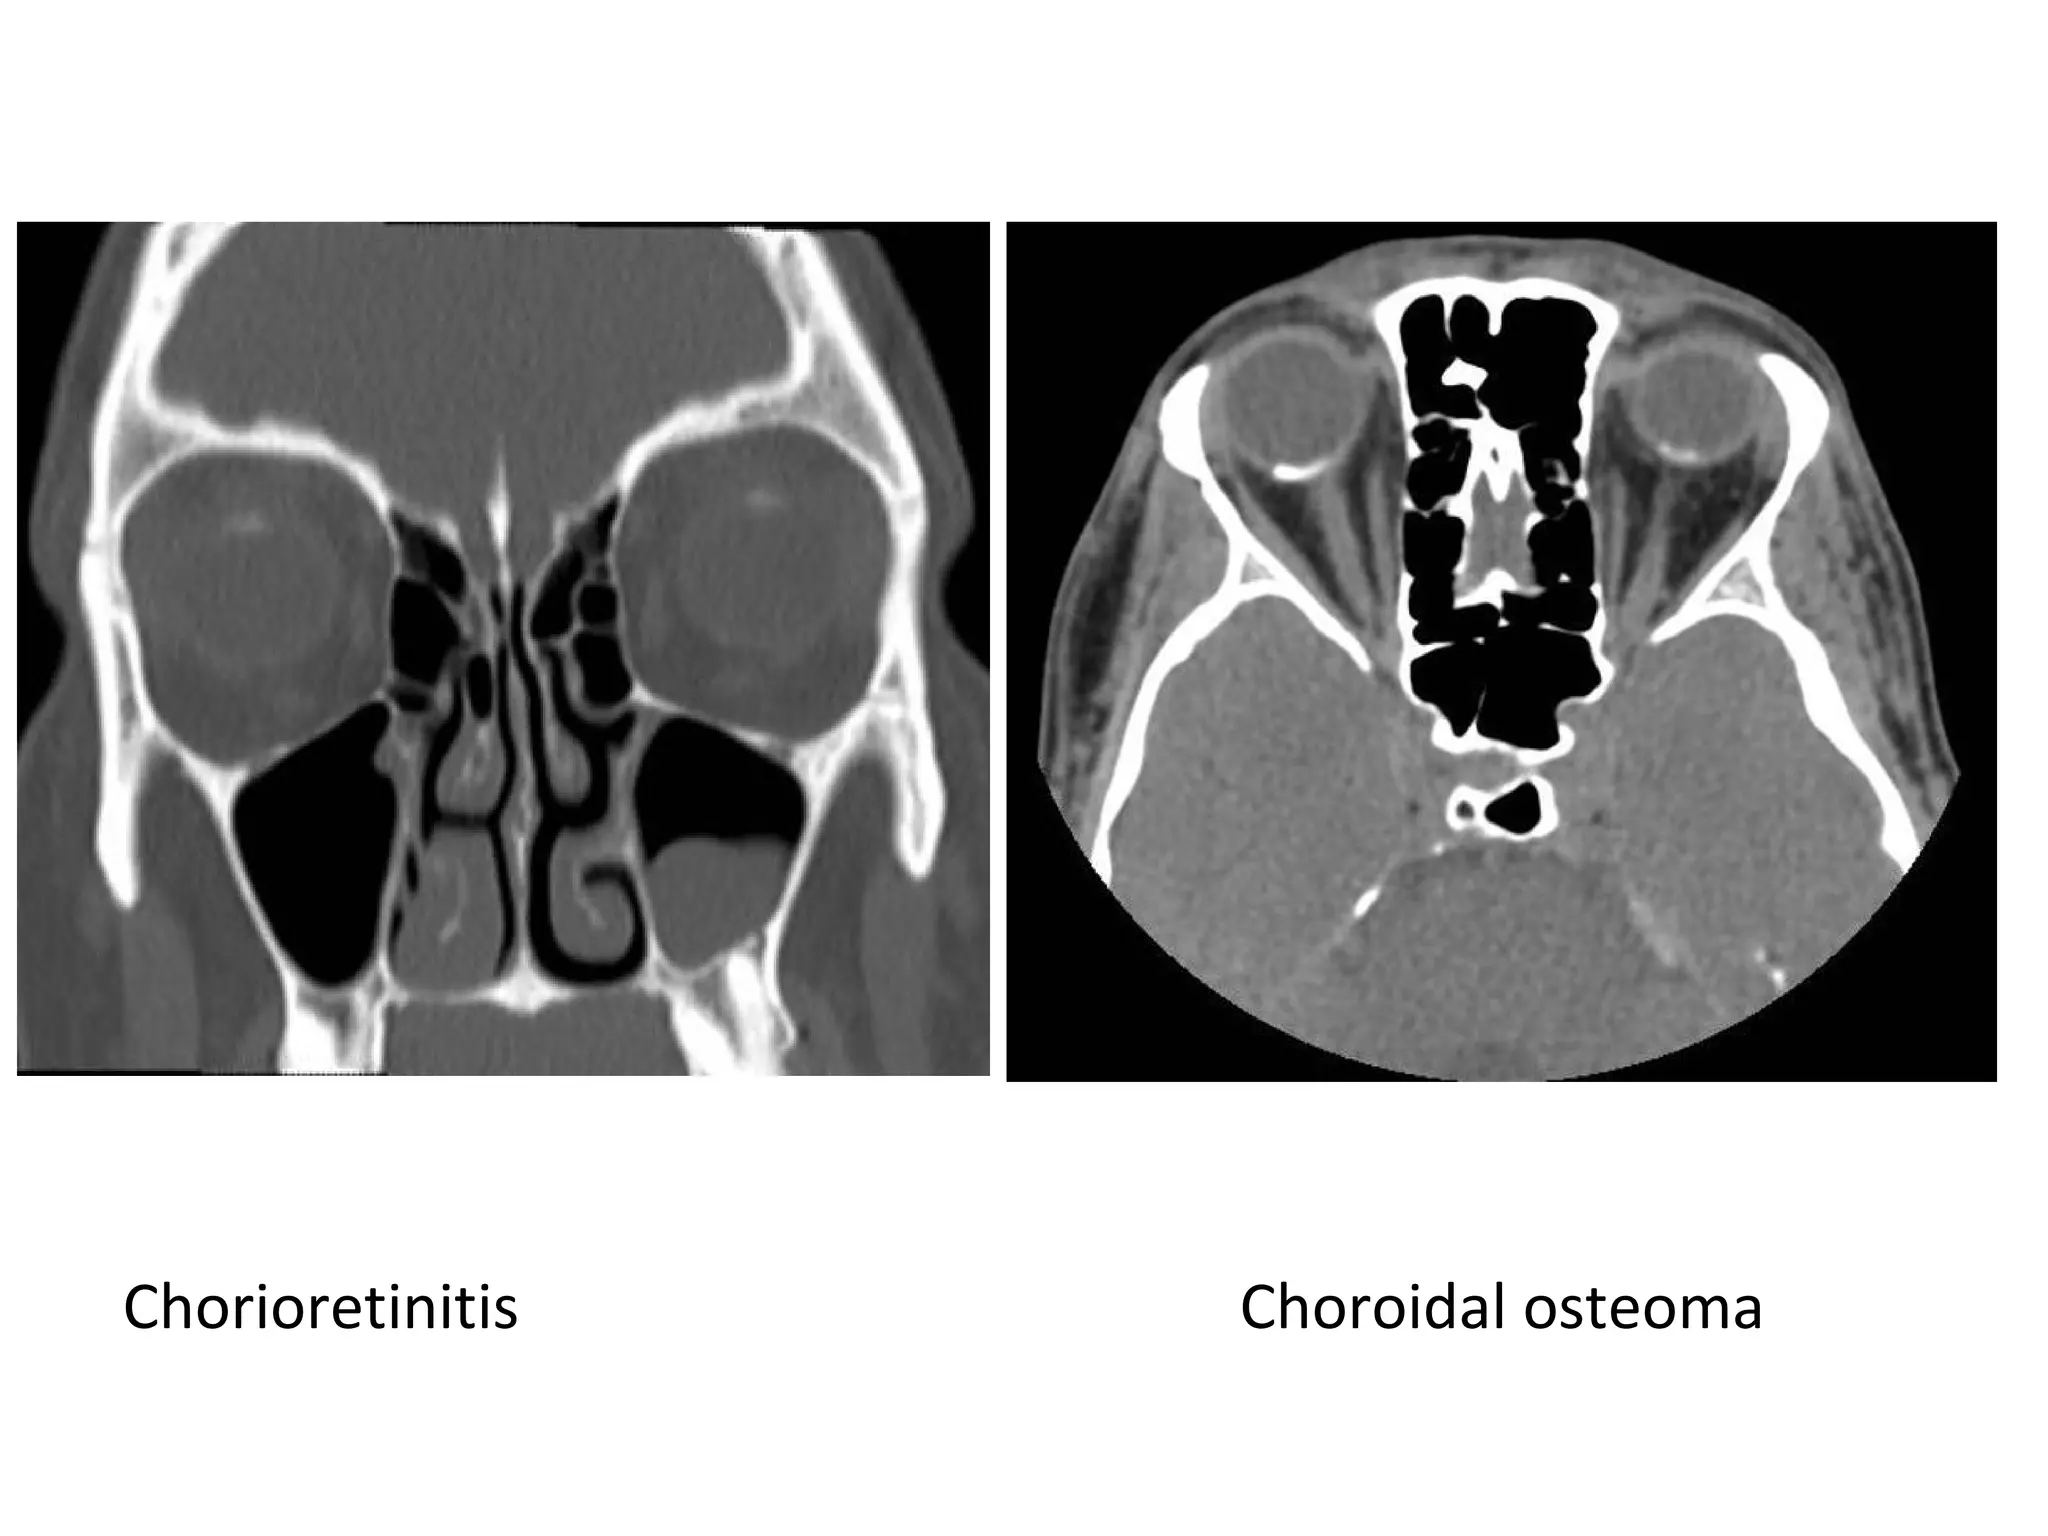

b) Retinochoroidal :

-Chorioretinitis : most commonly

c) Choroidal :

1-Choroidal osteoma : more common in patients

with tuberous sclerosis

2-Choroidal angioma : occasionally calcify

Chorioretinitis Choroidal osteoma